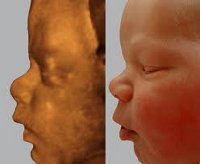

4D УЗИ - это видеосъемка плода через брюшную стенку матери с помощью ультразвуковых волн. Ультразвуковое исследование визуализирует плод, двигательную активность, черты лица. На 4D УЗИ врач может лучше рассмотреть пропорции, лицевой скелет и сделать выводы о двигательной активности.

Патологии развития плода можно выявить с помощью 3D и 4D УЗИ уже с 12 недели. На этом сроке можно обнаружить:

• дефекты формирования глаз, ушей, расщепление губ и неба;

• патологии развития костной системы;

• грыжи.